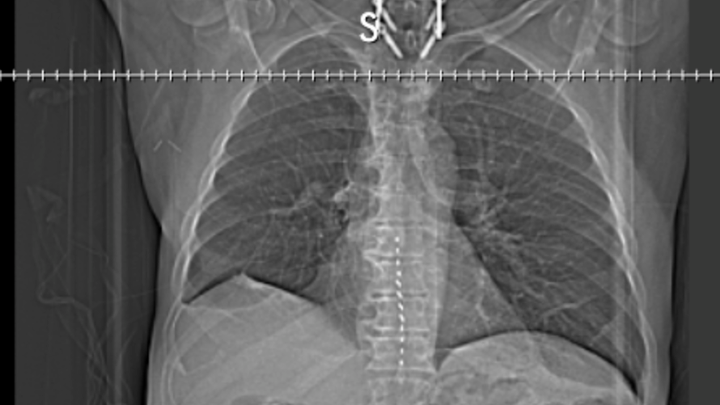

However, I have also been diagnosed with lung cancer that has spread locally to the thorax. It is considered locally spread, a Stage III diagnosis. The doctors believe there is a 20-30% chance of a cure with treatment, and we are committed to moving forward with the plan.

The most challenging chapter of my life began in August 2024, with a diagnosis of heart disease that required three stents. In November 2024, the situation escalated with a diagnosis of Large Cell Neuroendocrine Carcinoma Lung Cancer. Following a partial lung and lymph node removal in February 2025, we were overjoyed to hear that the lymph nodes were clear of cancer. We had hope that the Cancer was gone.

Unfortunately, in August 2025, the cancer returned aggressively, metastasizing to my thorax. Further imaging has shown new growths, so I am scheduled for more biopsies on October 31, 2025, to check if it has spread to my liver. My oncologist has given me a prognosis of 6 to 8 months without treatment. My current treatment plan is an intensive combination of chemotherapy and radiation, if the new growths are not more cancerous.